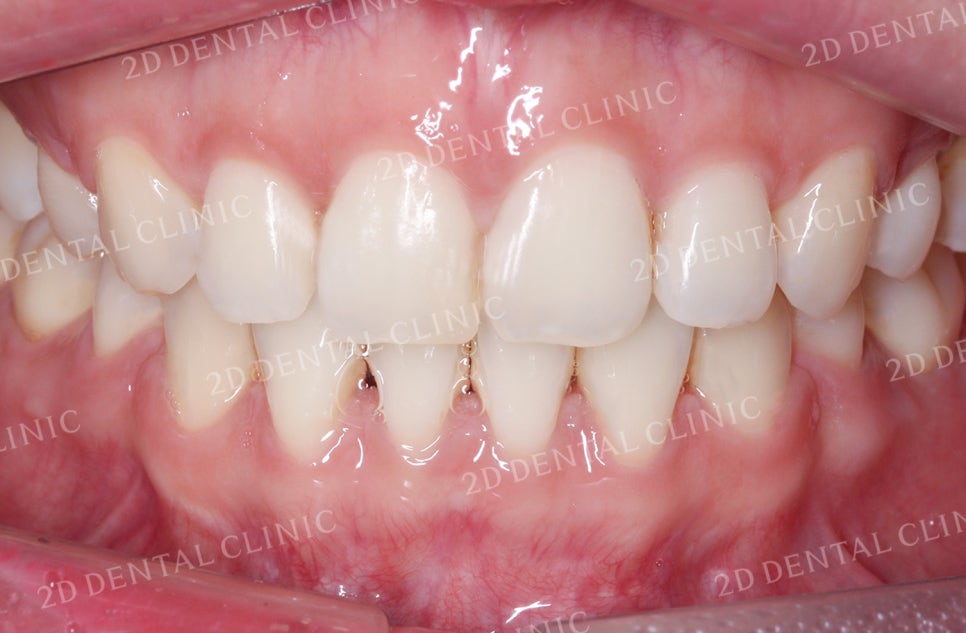

비대칭 돌출앞니 전체 교정 전

투디치과(2D치과)

비대칭앞니, 돌출앞니를 전체교정으로 교정하고 싶다면!? by.투디치과(2D치과)

비대칭 돌출앞니 교정 전 사진입니다.

11번 치아보다 21번 치아가

순측면으로 들려있는 것이 확인됩니다.

전치부의 치아들이 전체적으로

돌출된 형태인데요,

하악의 경우 비좁은 공간으로 인해

앞니의 총생까지 발견되고 있습니다.

또한 상악과 하악의 교합이 좋지 않아

교합면이 들뜨고 벌어진 모습이네요.